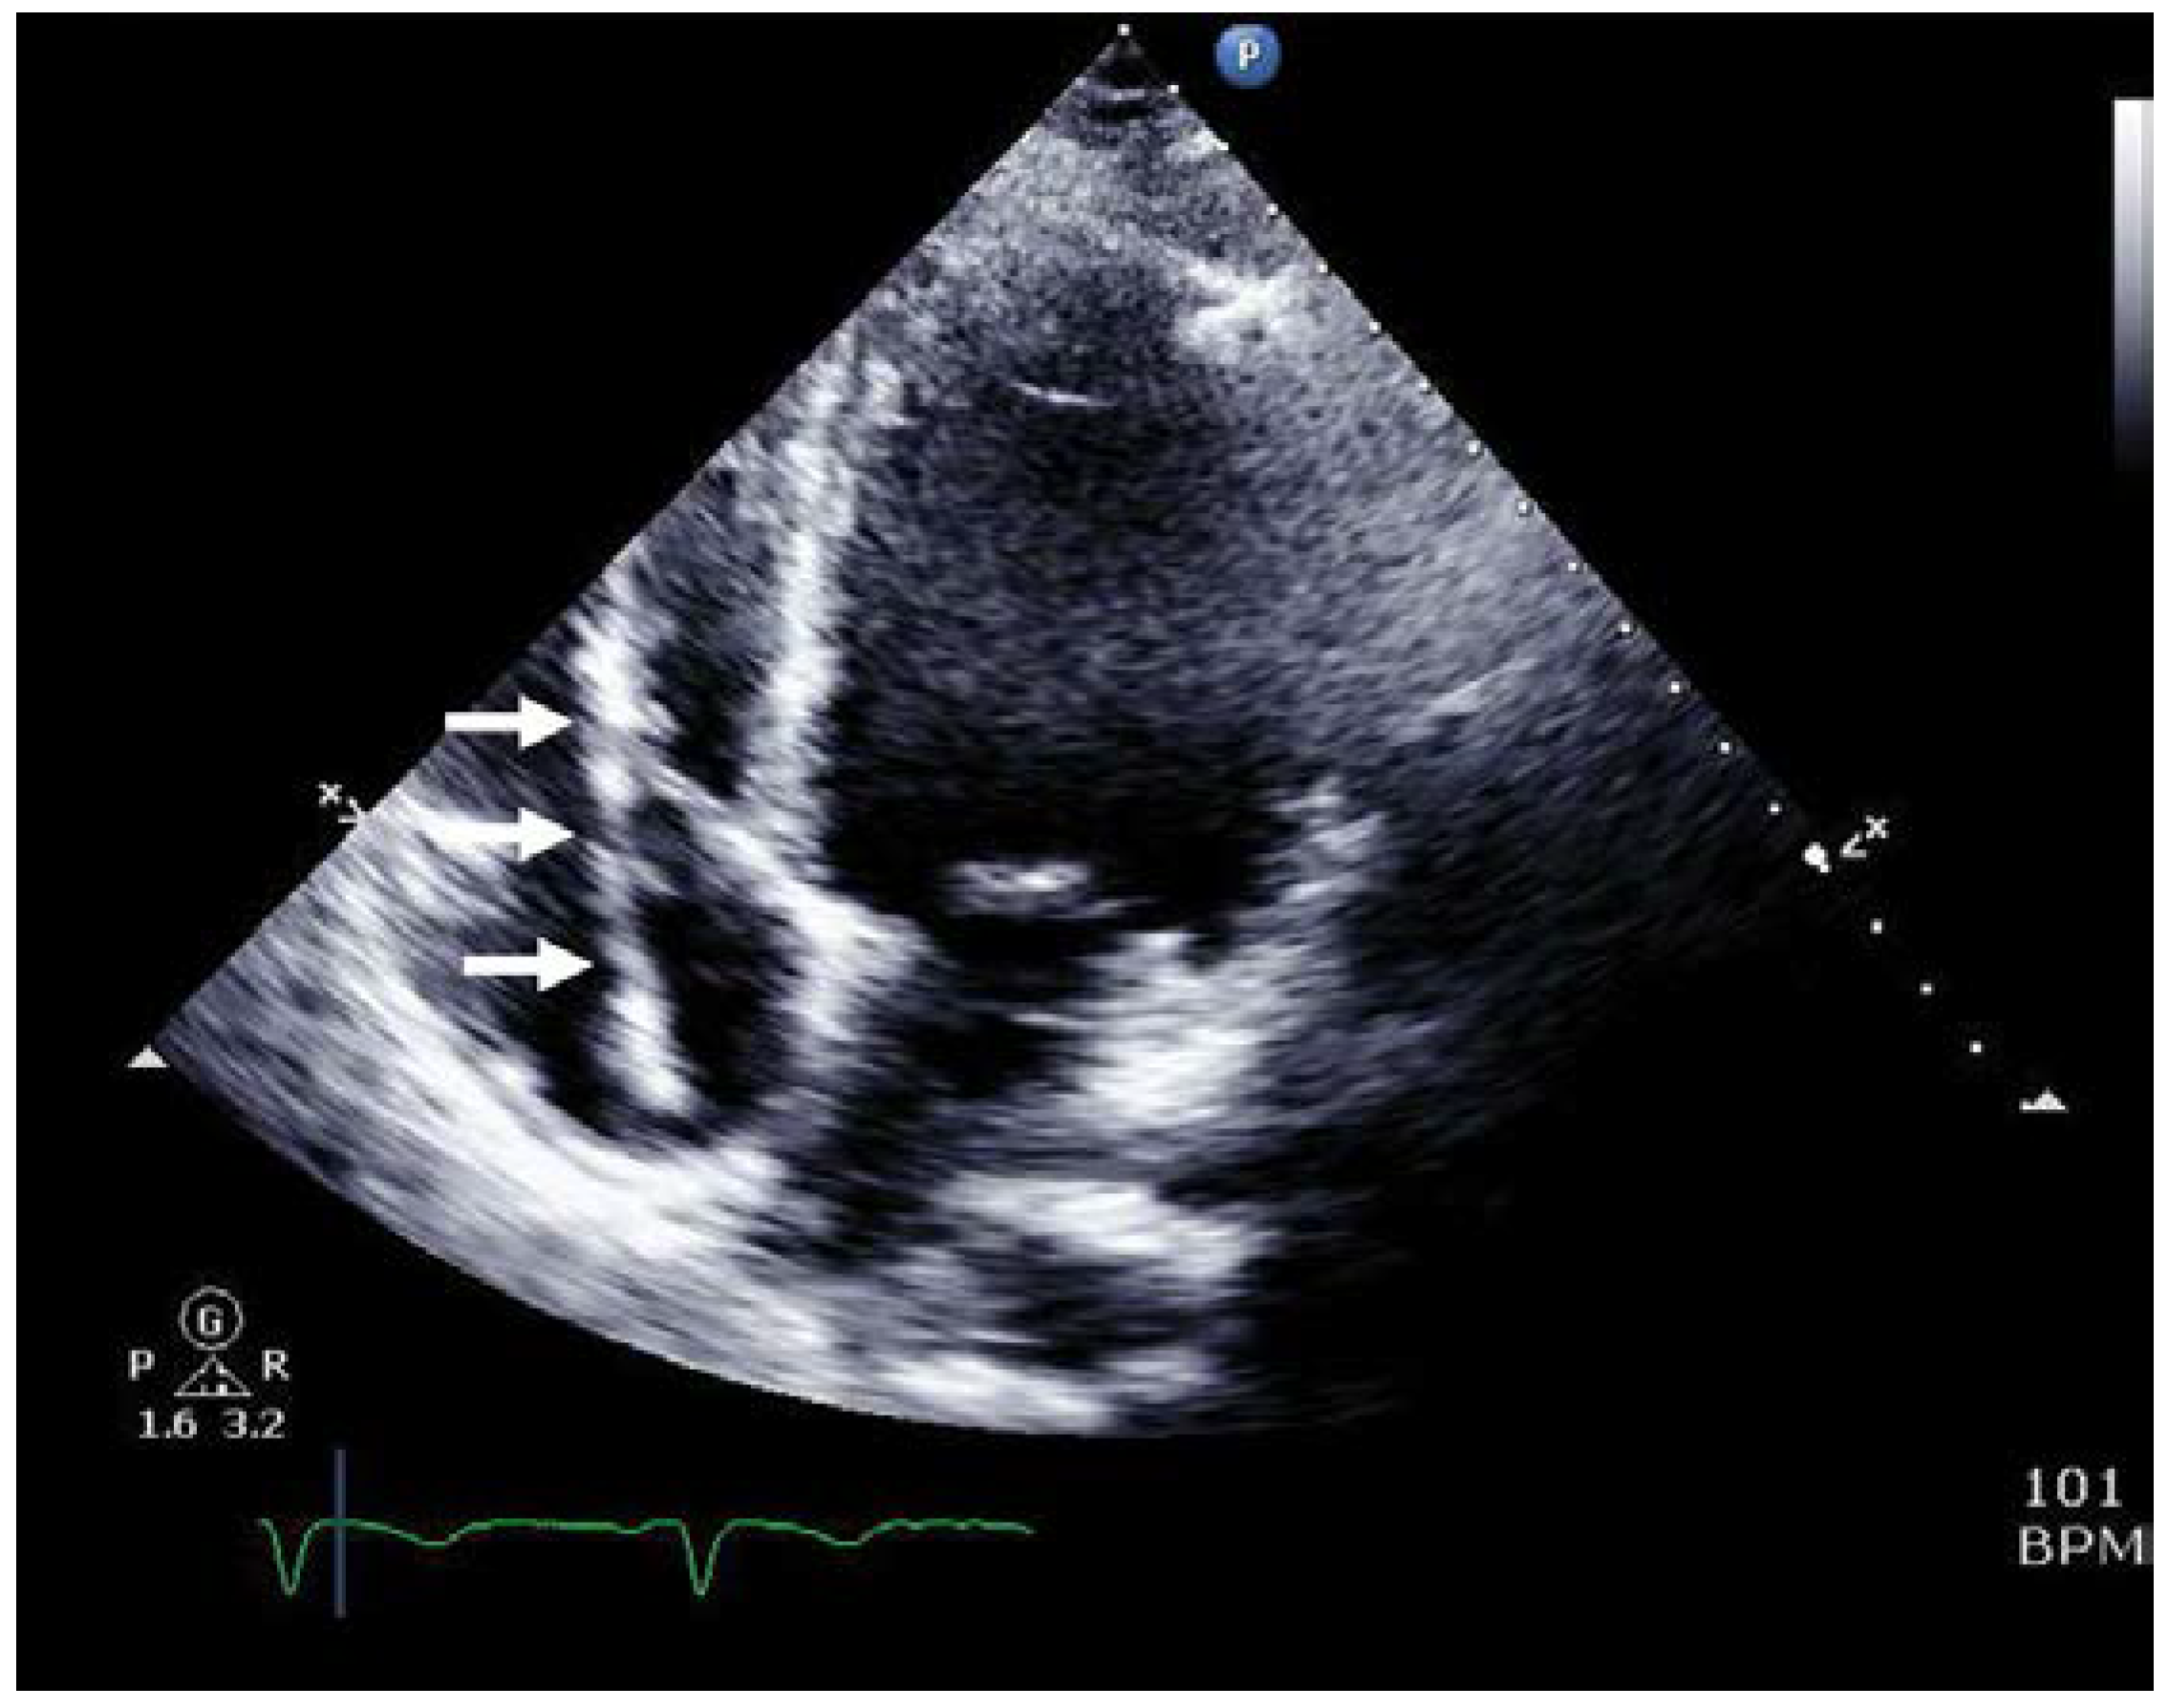

Case presentation